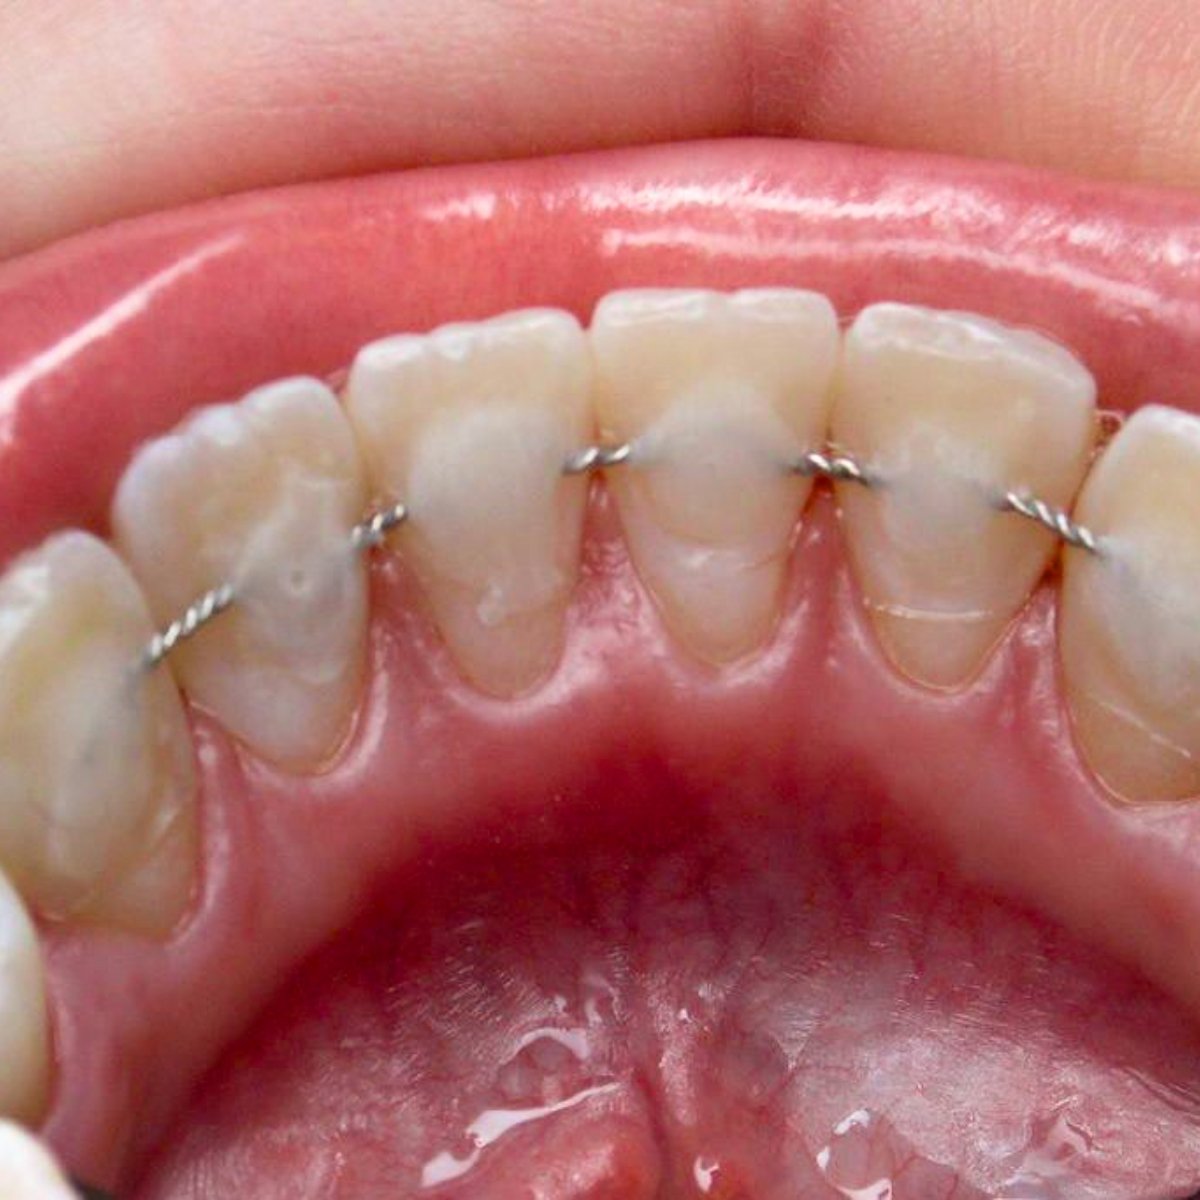

In some cases, splinting becomes an essential part of a much broader and more comprehensive periodontal treatment strategy. This approach may also include advanced procedures such as laser therapy to eliminate infection, curettage to remove diseased tissue, and bone regeneration techniques to rebuild lost bone structure. When we stabilize weakened teeth using a splint, we create a more favorable and stable environment that encourages healing. This support allows the surrounding tissues—especially the gums and bone—to regenerate and regain their strength. The success of splinting is significantly higher when inflammation has already been controlled and the oral environment is clean and healthy.

Additionally, splinting serves a valuable temporary function in more complex orthodontic or prosthetic treatment plans. For instance, when a patient is preparing to receive dental implants or bridges, stabilizing the current position of mobile or weakened teeth prevents undesired shifting or misalignment. This step is crucial in preserving the natural bite and spacing, which in turn contributes to the long-term success of the next phase of treatment. Whether used as a short-term solution or as part of a long-term periodontal rehabilitation plan, splinting offers both functional and esthetic benefits that help maintain oral health and prevent tooth loss.

preliminary local anesthesia

securely tie several teeth with tape

mobility is eliminated, inflammation disappears

gum is restored